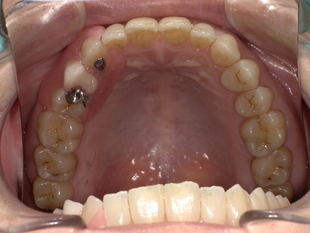

■ 【Before→After】ノンクラスプ義歯で口元の印象が大きく若返り

▼ 治療前

-

歯の欠損部の影響で口元がへこみ、老けた印象

バネ式の入れ歯では金具が見えてしまう

噛み合わせが不安定で、しっかり食べられない

■ 【治療概要】

年齢・性別:50代女性

診療種別:自由診療(ノンクラスプ義歯)

治療期間:約3週間

治療回数:5回

治療費総額:398,200円(税込)